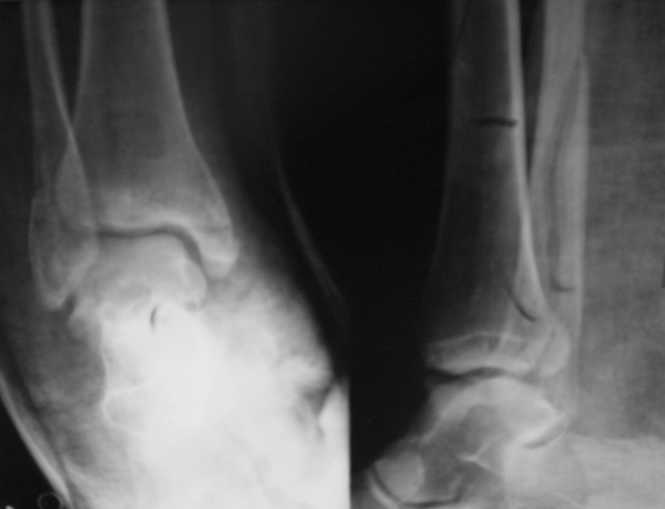

Вот рентгенконтроль на 7-е сутки после репозиции.